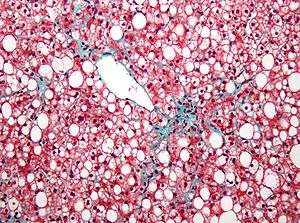

| Micrograph of non-alcoholic fatty liver disease | |

- Fatty liver disease (hepatic steatosis) is a reversible condition where large vacuoles of triglyceride fat accumulate in liver cells.[6] Non-alcoholic fatty liver disease is a spectrum of disease associated with obesity and metabolic syndrome.[7]